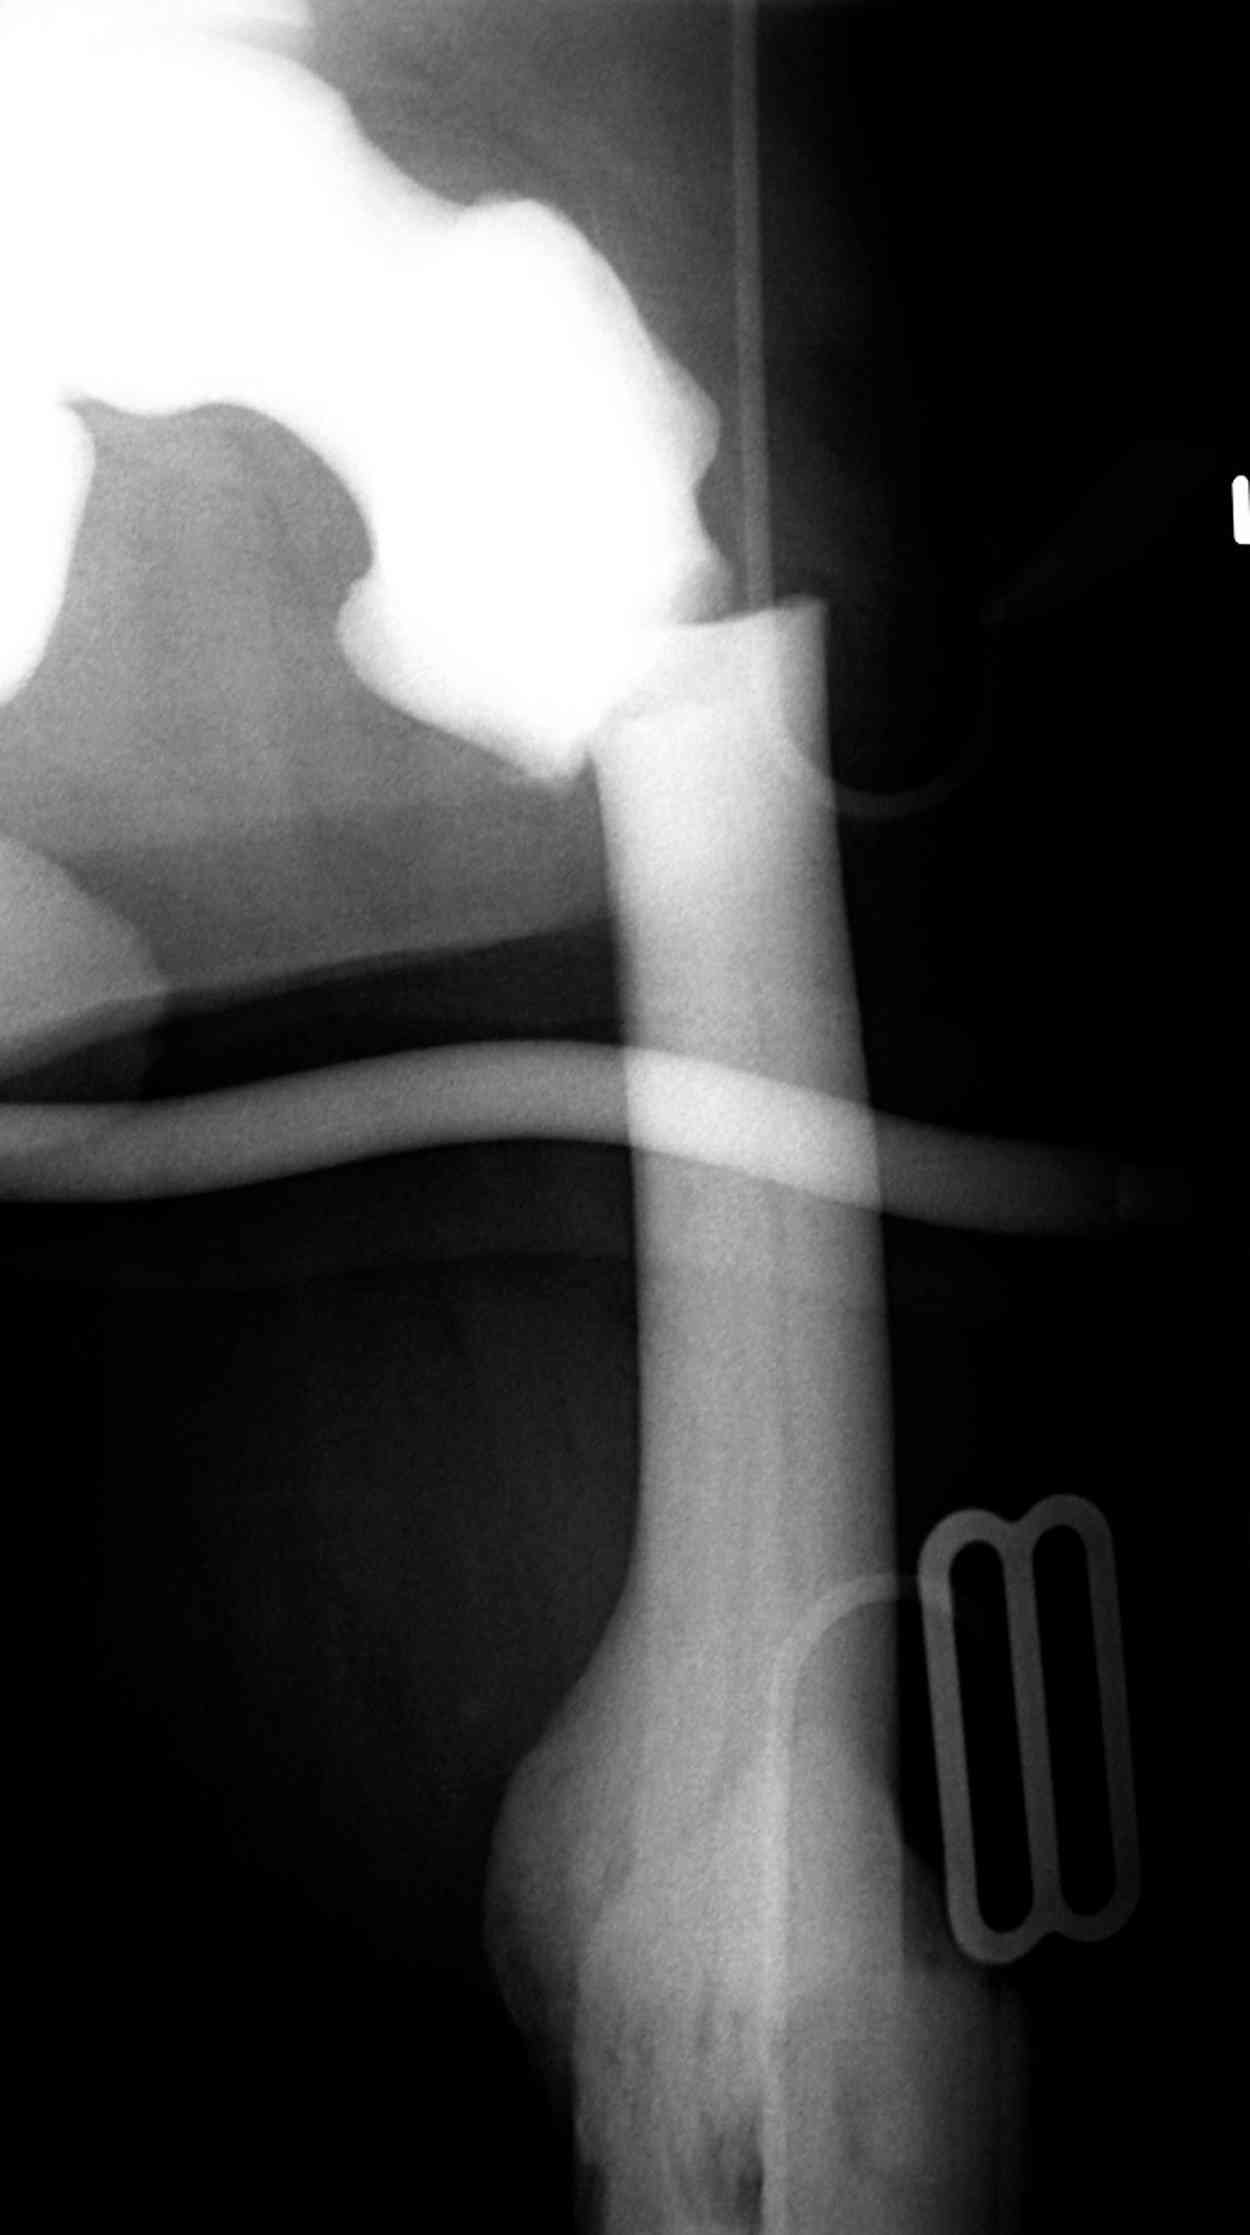

Мужчина, 53 года, жалуется на постоянные ноющие боли в костях голеней, усиливающиеся после ходьбы, боли в коленных суставах. Считает себя больным с 1987 г., когда впервые появились боли в коленных суставах. В 1990 г. выставлен д-з: вторичный ДОА коленных суставов, фиброзная дисплазия костей. После проведенного лечения (НПВП, радоновые ванны, курс введения кислорода в коленные суставы) в течение 5 лет ремиссия. С 1995 г. ежегодные обострения весной и осенью, проявляющиеся болями в коленных суставах, явлениями синовита. Проводилось лечение НПВП, физиопроцедуры, внутрисуставное введение дипроспана с положительным эффектом. С 2004 г. - эффекта от проводимой терапии нет. В 2006 г. впервые по рентгеновским снимкам выставлен д-з: болезнь Альберса-Шенберга. Деформирующий гонартроз справа 2 ст., слева 3 ст. С 2006 г. ездит на лечение в Китай, где проводится лечение радоновыми грязями, массаж с положительным эффектом. Объективно: коленные суставы деформированы, при пальпации б/болезненные. Движения в полном объеме. При ходьбе хромает. Диагноз: болезнь Алберс-Шонберга. Деформирующий гонартроз справа 2 ст., слева 3 ст.Хотелось бы уточнить диагноз и определить тактику дальнейшего лечения. Заранее спасибо.

Представленные Вами данные о пациенте 57 дет с болезнью Альбертс-Шенберга чрезвычайно интересны, но диагноз вызывает большие сомнения. Для мраморной болезни характерно прееобладание склероза, а на представленных рентгенограммах преобладает симметричная дезорганизация архитектоники губчатой кости в эпиметафизарной зоне дистальных отделов бедер и голеней.

Мне кажется, представленные рентгенограммы скорее соответствуют варианту фиброзной дисплазии который был описан М. Campanacci (1976) или

обызвествляющей фиброме H.E.Schlitter (1958).

Уважаемый Константин Иванович! Полностью согласен с проф. Михайловым, данный случай не похож на мраморную болезнь, при которой имеется резкое, строго симметричное и генерализованное уплотнение костной ткани (остеопетроз), и кость оказывается построенной преимущественно из гомогенного компактного костного вещества. Для примера привожу случай из архива нашего института (бедренные, плечевые кости и таз, рис 1,2,3)

Изменения структуры костей у Вашего пациента больше похожи на полиоссальную форму фиброзной дисплазии или болезнь Педжета, возможены также инфаркты костного мозга б.берцовых костей. К сожалению, качество снимка не очень хорошее, непонятно, сохранен ли кортикальный слой б.берцовых костей по передней поверхности.

Не являюсь специалистом по костной патологии, но мне кажется, на ренгенограмме множественные мета-диафизарные образования напоминяющее змееподобных извилистых линии и периостеальные ламинирование очень напоминяет картину остеонекроза (инфаркта) костей, возможно связано с длительным применением стероидов.